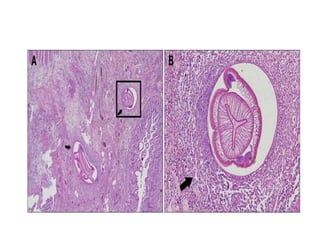

Echinococosis

• Caused by Dog tapeworm in larval or cystic stage: E.

granulosus (causes cystic hydatid disease), less

commonly E. multilocularis (alveolar hydatid disease),

or E. vogeli (polycystic hydatid disease).

• 3 layers in cyst wall:

● (a) innermost (germinal layer) is 10-25 microns,

contains nuclei, gives rise to brood capsules and

protoscolices

● (b) laminated membrane beneath germinal layer is 1

mm thick, avascular, eosinophilic, refractile and

chitinous; strongly PAS+, GMS+

● (c) outer layer is dense fibrovascular tissue with

chronic inflammatory cells, variable calcification

develops after 5+ years

Echinococosis • Caused byDog tapeworm in larval or cystic stage: E. granulosus (causes cystic hydatid disease), less commonly E. multilocularis (alveolar hydatid disease), or E. vogeli (polycystic hydatid disease). • 3 layers in cyst wall: ● (a) innermost (germinal layer) is 10-25 microns, contains nuclei, gives rise to brood capsules and protoscolices ● (b) laminated membrane beneath germinal layer is 1 mm thick, avascular, eosinophilic, refractile and chitinous; strongly PAS+, GMS+ ● (c) outer layer is dense fibrovascular tissue with chronic inflammatory cells, variable calcification develops after 5+ years